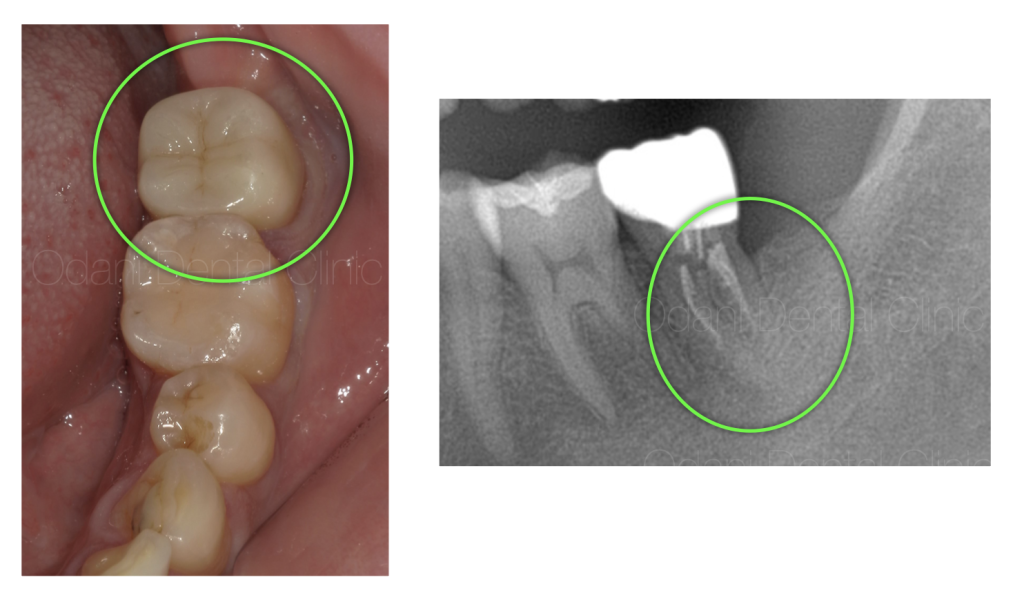

治療終了時の状態

根管治療後、 術後3ヶ月な状態です。黒い影がなくなり、骨が回復している様子が伺えます。

痛みや腫れ等の症状も全てなくなったため、最終のかぶせ物の治療を行いました。